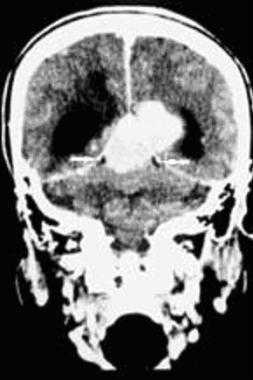

З адняя тенториальная менингиома на корональном КТ-изображении с контрастным усилением. К намету мозжечка прилежит объемное образование повышенной плотности с четкими краями. Визуализируются застой спинно-мозговой жидкости, легкий отек прилежащих тканей, гомогенный характер контрастирования, а также расширение желудочков.

Метастазы головного мозга, фото. На КТ с контрастным усилением у пожилой пациентки (в верхнем ряду слева) с жалобами на головные боли выявлены множественные объемные образования в левом полушарии мозга, интенсивно накапливающие контрастное вещество. Образования имеют характерную форму в виде «кольца». На изображениях в нижнем ряду и вверху справа определяются множественные очаги в головном мозге: отчетливо видны округлые образования с более плотным «ободком» по периферии, располагающиеся в левой теменной доле.